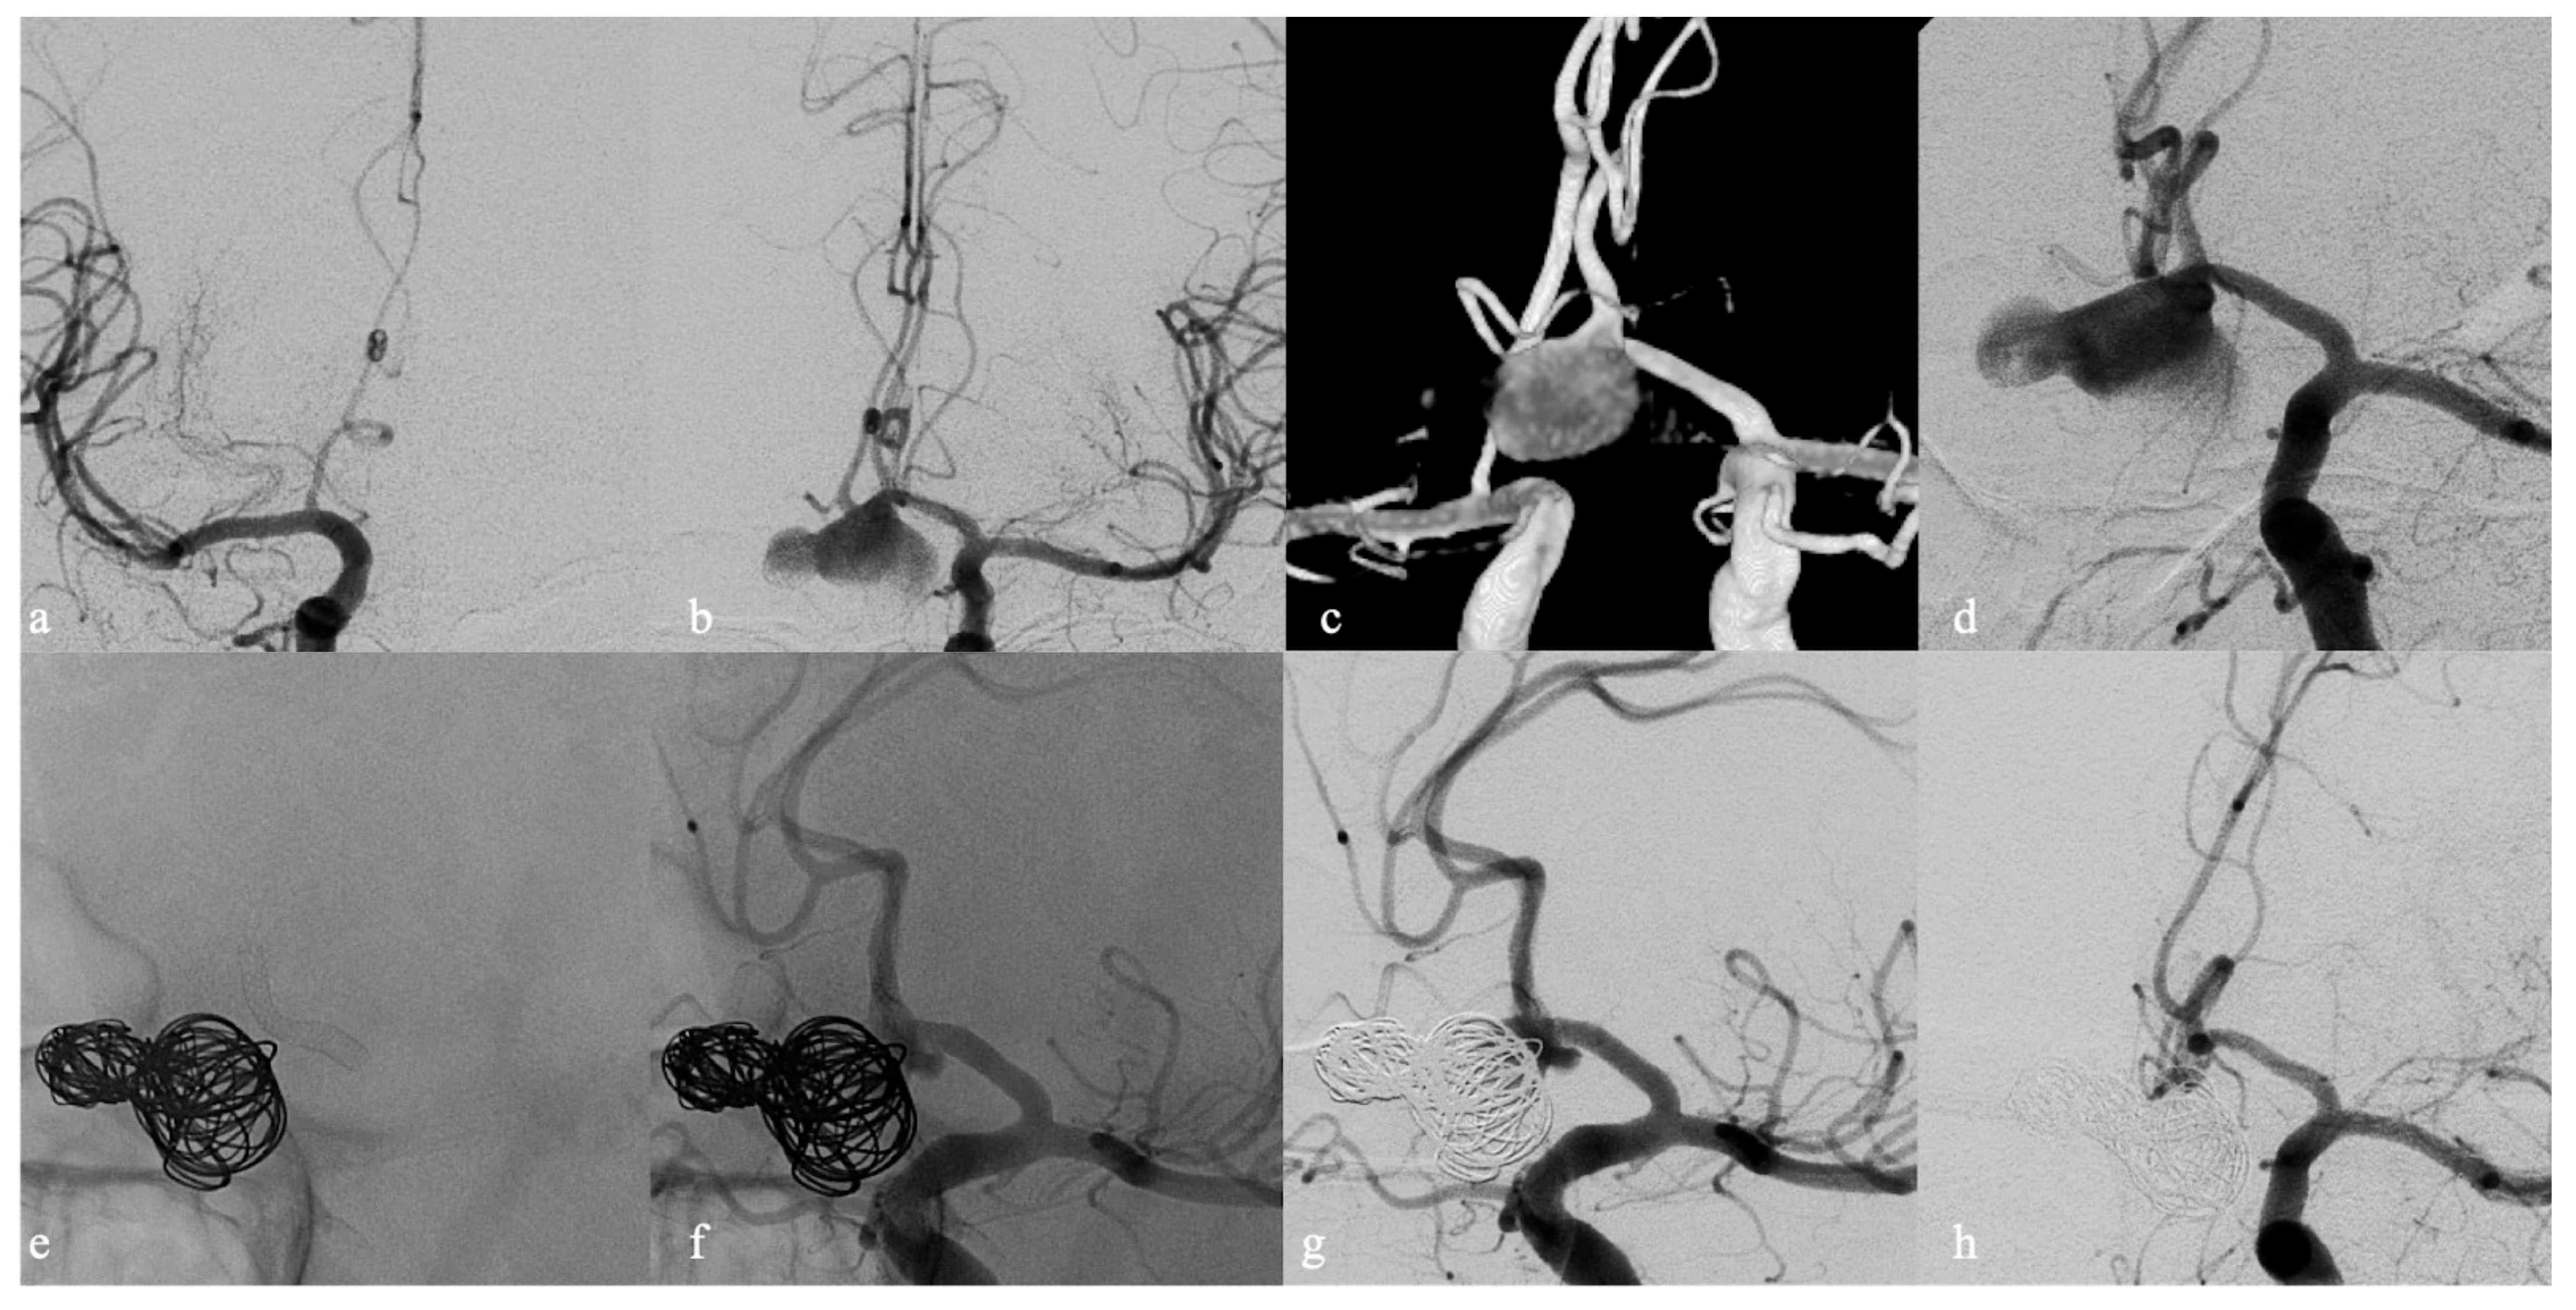

- Brinjikji, W.; Piano, M.; Fang, S.; Pero, G.; Kallmes, D.F.; Quilici, L.; Valvassori, L.; Lozupone, E.; Cloft, H.J.; Boccardi, E.; et al. Treatment of ruptured complex and large/giant ruptured cerebral aneurysms by acute coiling followed by staged flow diversion. J. Neurosurg. 2016, 125, 120–127. [Google Scholar] [CrossRef]